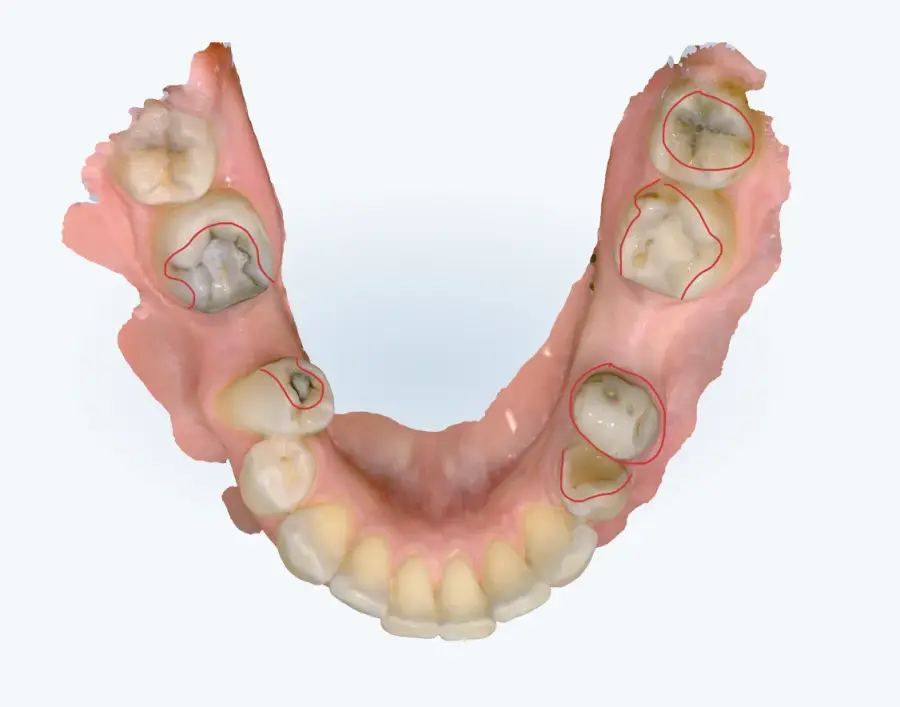

Papildus norādām, ka arī no intraorālās skenēšanas datiem (tostarp ekrānšāviņiem) ir identificējamas vairākas klīniski nozīmīgas problēmas, tai skaitā:

* aktīvi kariozi bojājumi,

* bojātas, lūzušas un plaisājušas plombes,

* vairāku zobu audu apjoma zudums,

* citas strukturālas izmaiņas, kas var ietekmēt turpmāko ortodontisko ārstēšanu.

Šie konstatējumi ir būtiski, jo pirms ortodontiskas ārstēšanas uzsākšanas ir nepieciešams nodrošināt mutes dobuma veselības stabilitāti, kas ir starptautiski pieņemta un medicīniski pamatota prakse.